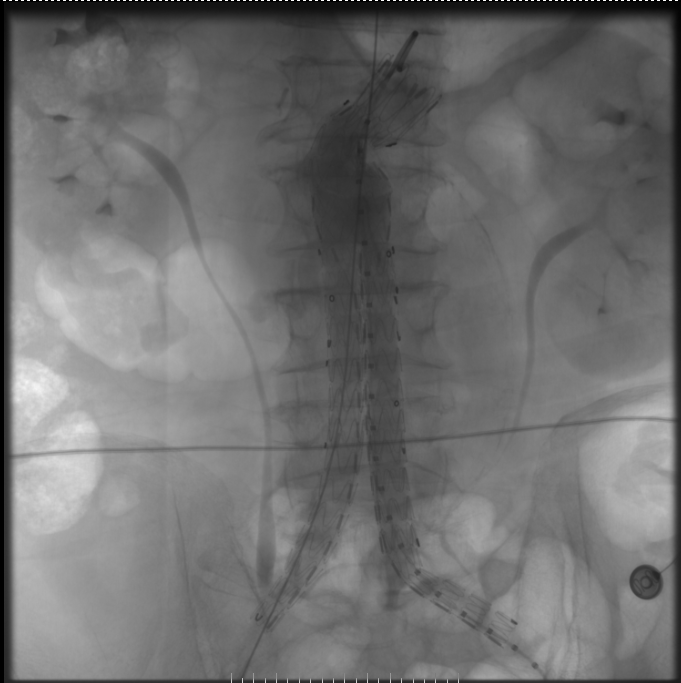

血管造影“人”字形支架放入血管

SICU医护人员立即完善术前准备,胸外科李凯主任团队凭借着丰富的经验和熟练的技术,从容地进行手术,麻醉科许少华医师保驾护航,顺利完成手术。